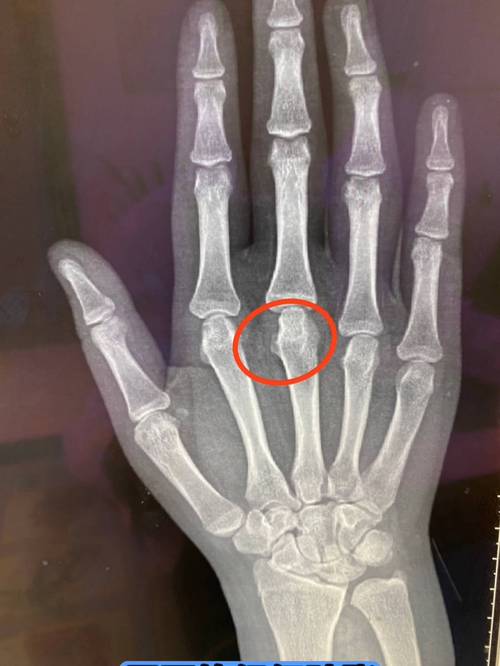

- 影像学检查:

- X光片: 主要用于观察关节有无骨质破坏、发育异常等晚期改变。